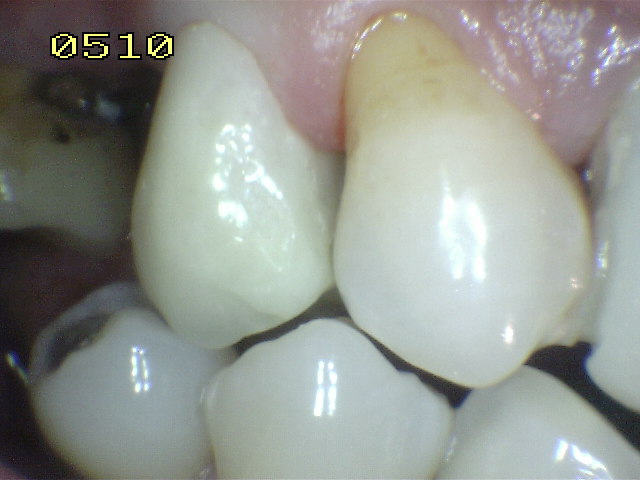

En la imagen superior se ha realizado un tratamiento de conducto y un perno muñón colado. En la siguiente se observa una corona provisoria realizada en acrílico de termocurado.